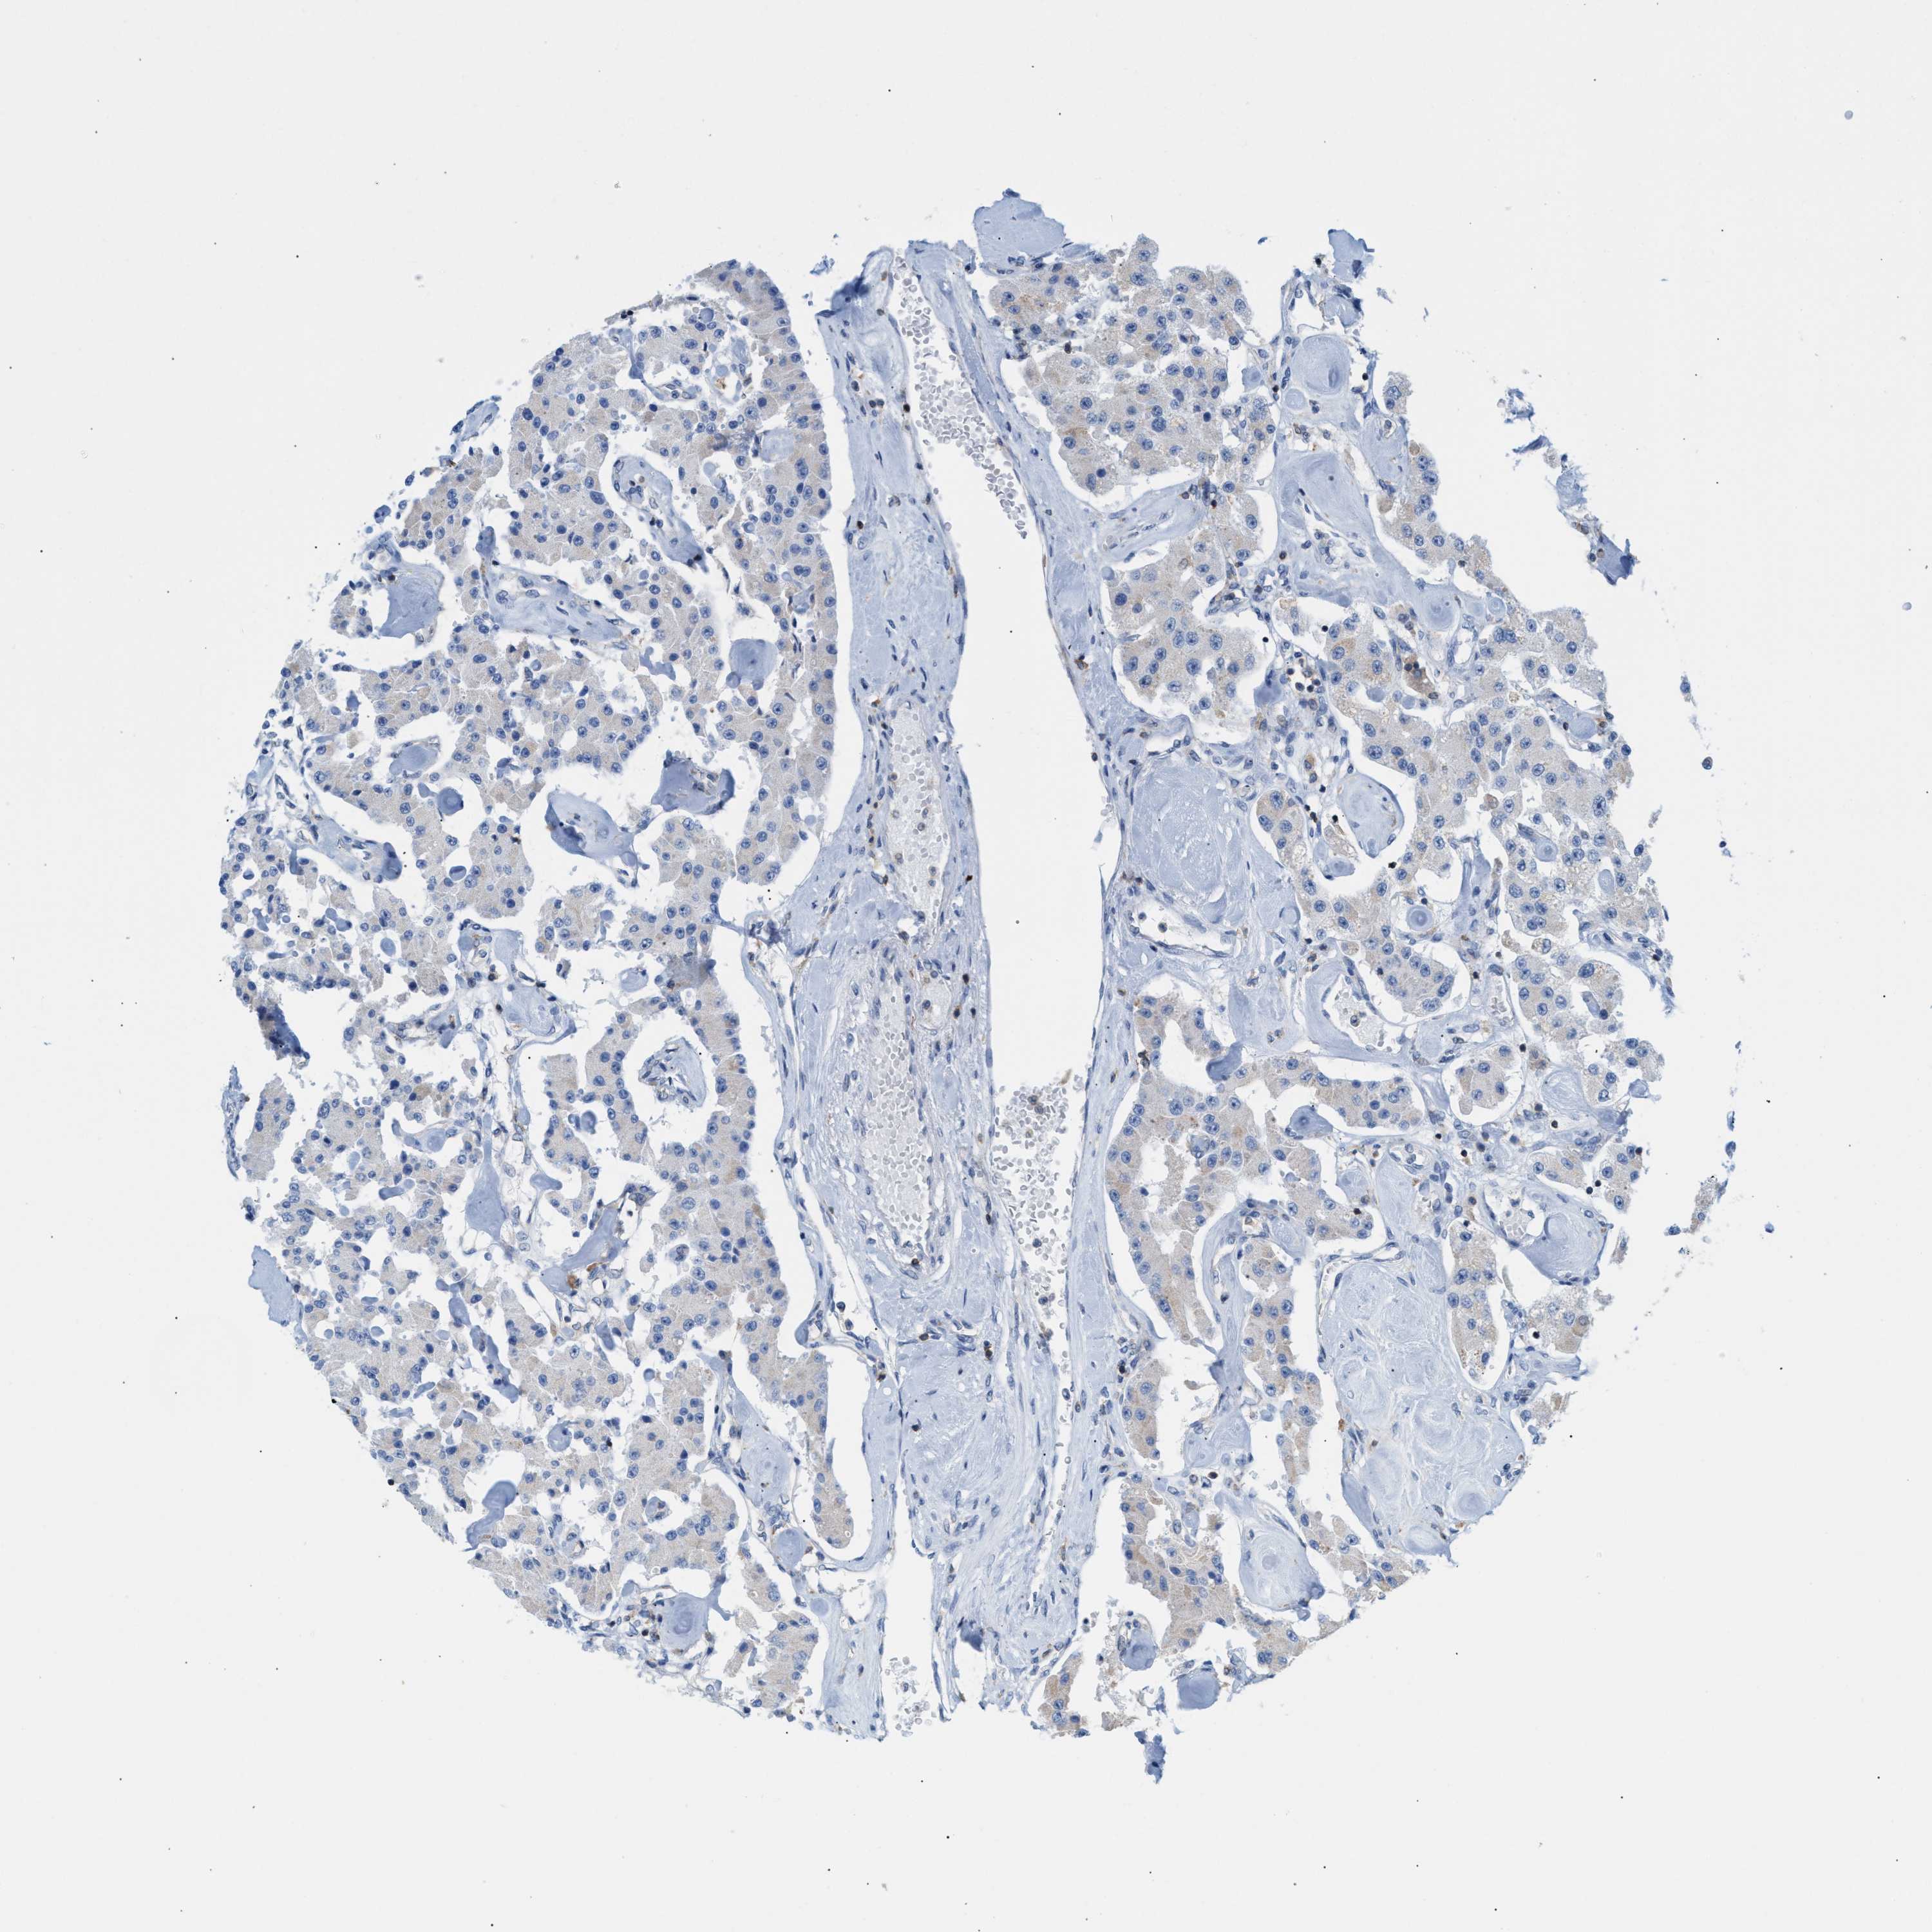

CARCINOID - Protein expressioni

A mouse-over function shows sample information and annotation data. Click on an image to view it in a full screen mode. Samples can be filtered based on level of antibody staining by selecting one or several of the following categories: high, medium, low and not detected. The assay and annotation is described here.

Antibody stainingi

Antibody staining in the annotated cell types in the current human tissue is reported as not detected, low, medium, or high, based on conventional immunohistochemistry profiling in selected tissues. This score is based on the combination of the staining intensity and fraction of stained cells.

Each image is clickable and will lead to virtual microscopy that enables deeper exploration of all samples and also displays staining intensity scores, fraction scores and subcellular localization as well as patient and tissue information for each sample.

Antibody HPA018467

Carcinoid, malignant, NOS